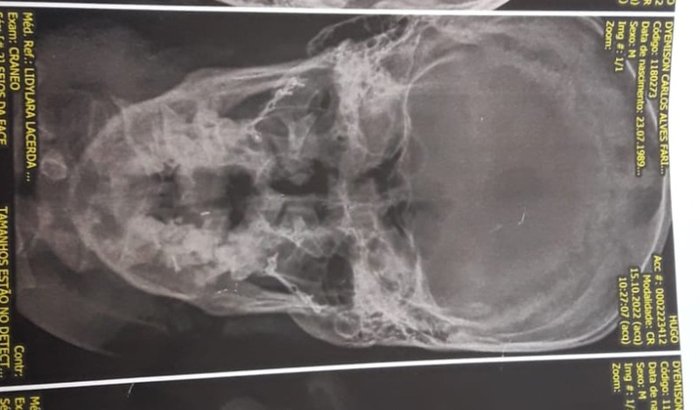

NOSSO AMIGO DYEMISON DA SAD MOTOS  SOFREU UM ACIDENTE NO DIA 9 DE OUTUBRO,  QUEBROU MANDÍBULA, NARIZ DENTES E RACHOU O CRÂNIO. DYEMISON TEM 2 FILHOS E UMA ESPOSA, SUSTENTA CASA SOZINHO E NÃO CONSEGUE TRABALHAR AINDA. ver tudo

NOSSO AMIGO DYEMISON DA SAD MOTOS  SOFREU UM ACIDENTE NO DIA 9 DE OUTUBRO,  QUEBROU MANDÍBULA, NARIZ DENTES E RACHOU O CRÂNIO. DYEMISON TEM 2 FILHOS E UMA ESPOSA, SUSTENTA CASA SOZINHO E NÃO CONSEGUE TRABALHAR AINDA. QUEM QUISER VER LAUDOS CHAMA NO ZAP: 61 9 8456-1094